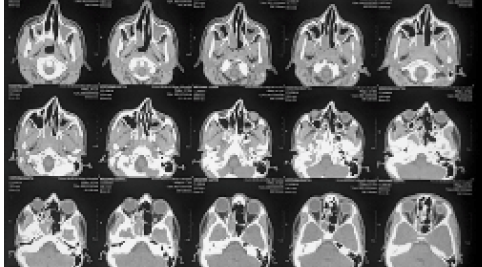

Nasalactinomycosis Mimicking Juvenile Nasopharyngeal Angiofibroma

Kalpana Sharma, Uma Roy, KumKum Bora, Navroz Mehta